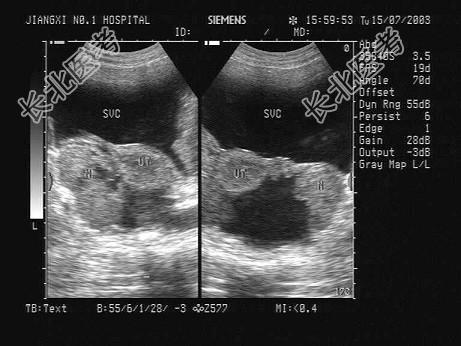

- 单项选择题某患者因下腹胀痛就诊,HCG(-), 声像图如下,最可能的诊断是   (   )

A、盆腔积液

B、宫外孕

C、卵巢癌

D、附件炎

E、卵巢囊肿